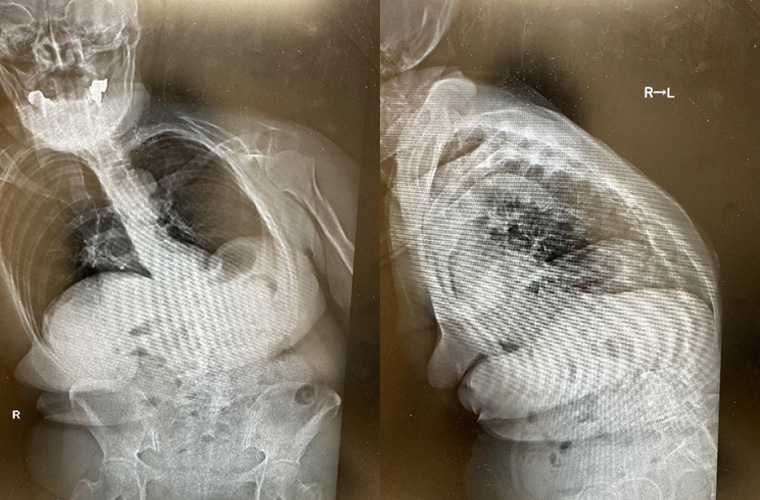

成人脊柱変形に対する治療を行った画像の変化を紹介いたします。

左写真:画像上ひだり側(体としては右)に曲がっています。

左写真:画像上ひだり側(体としては右)に曲がっています。右写真:側面像です。立位で撮影し前に体が倒れてしまっています。